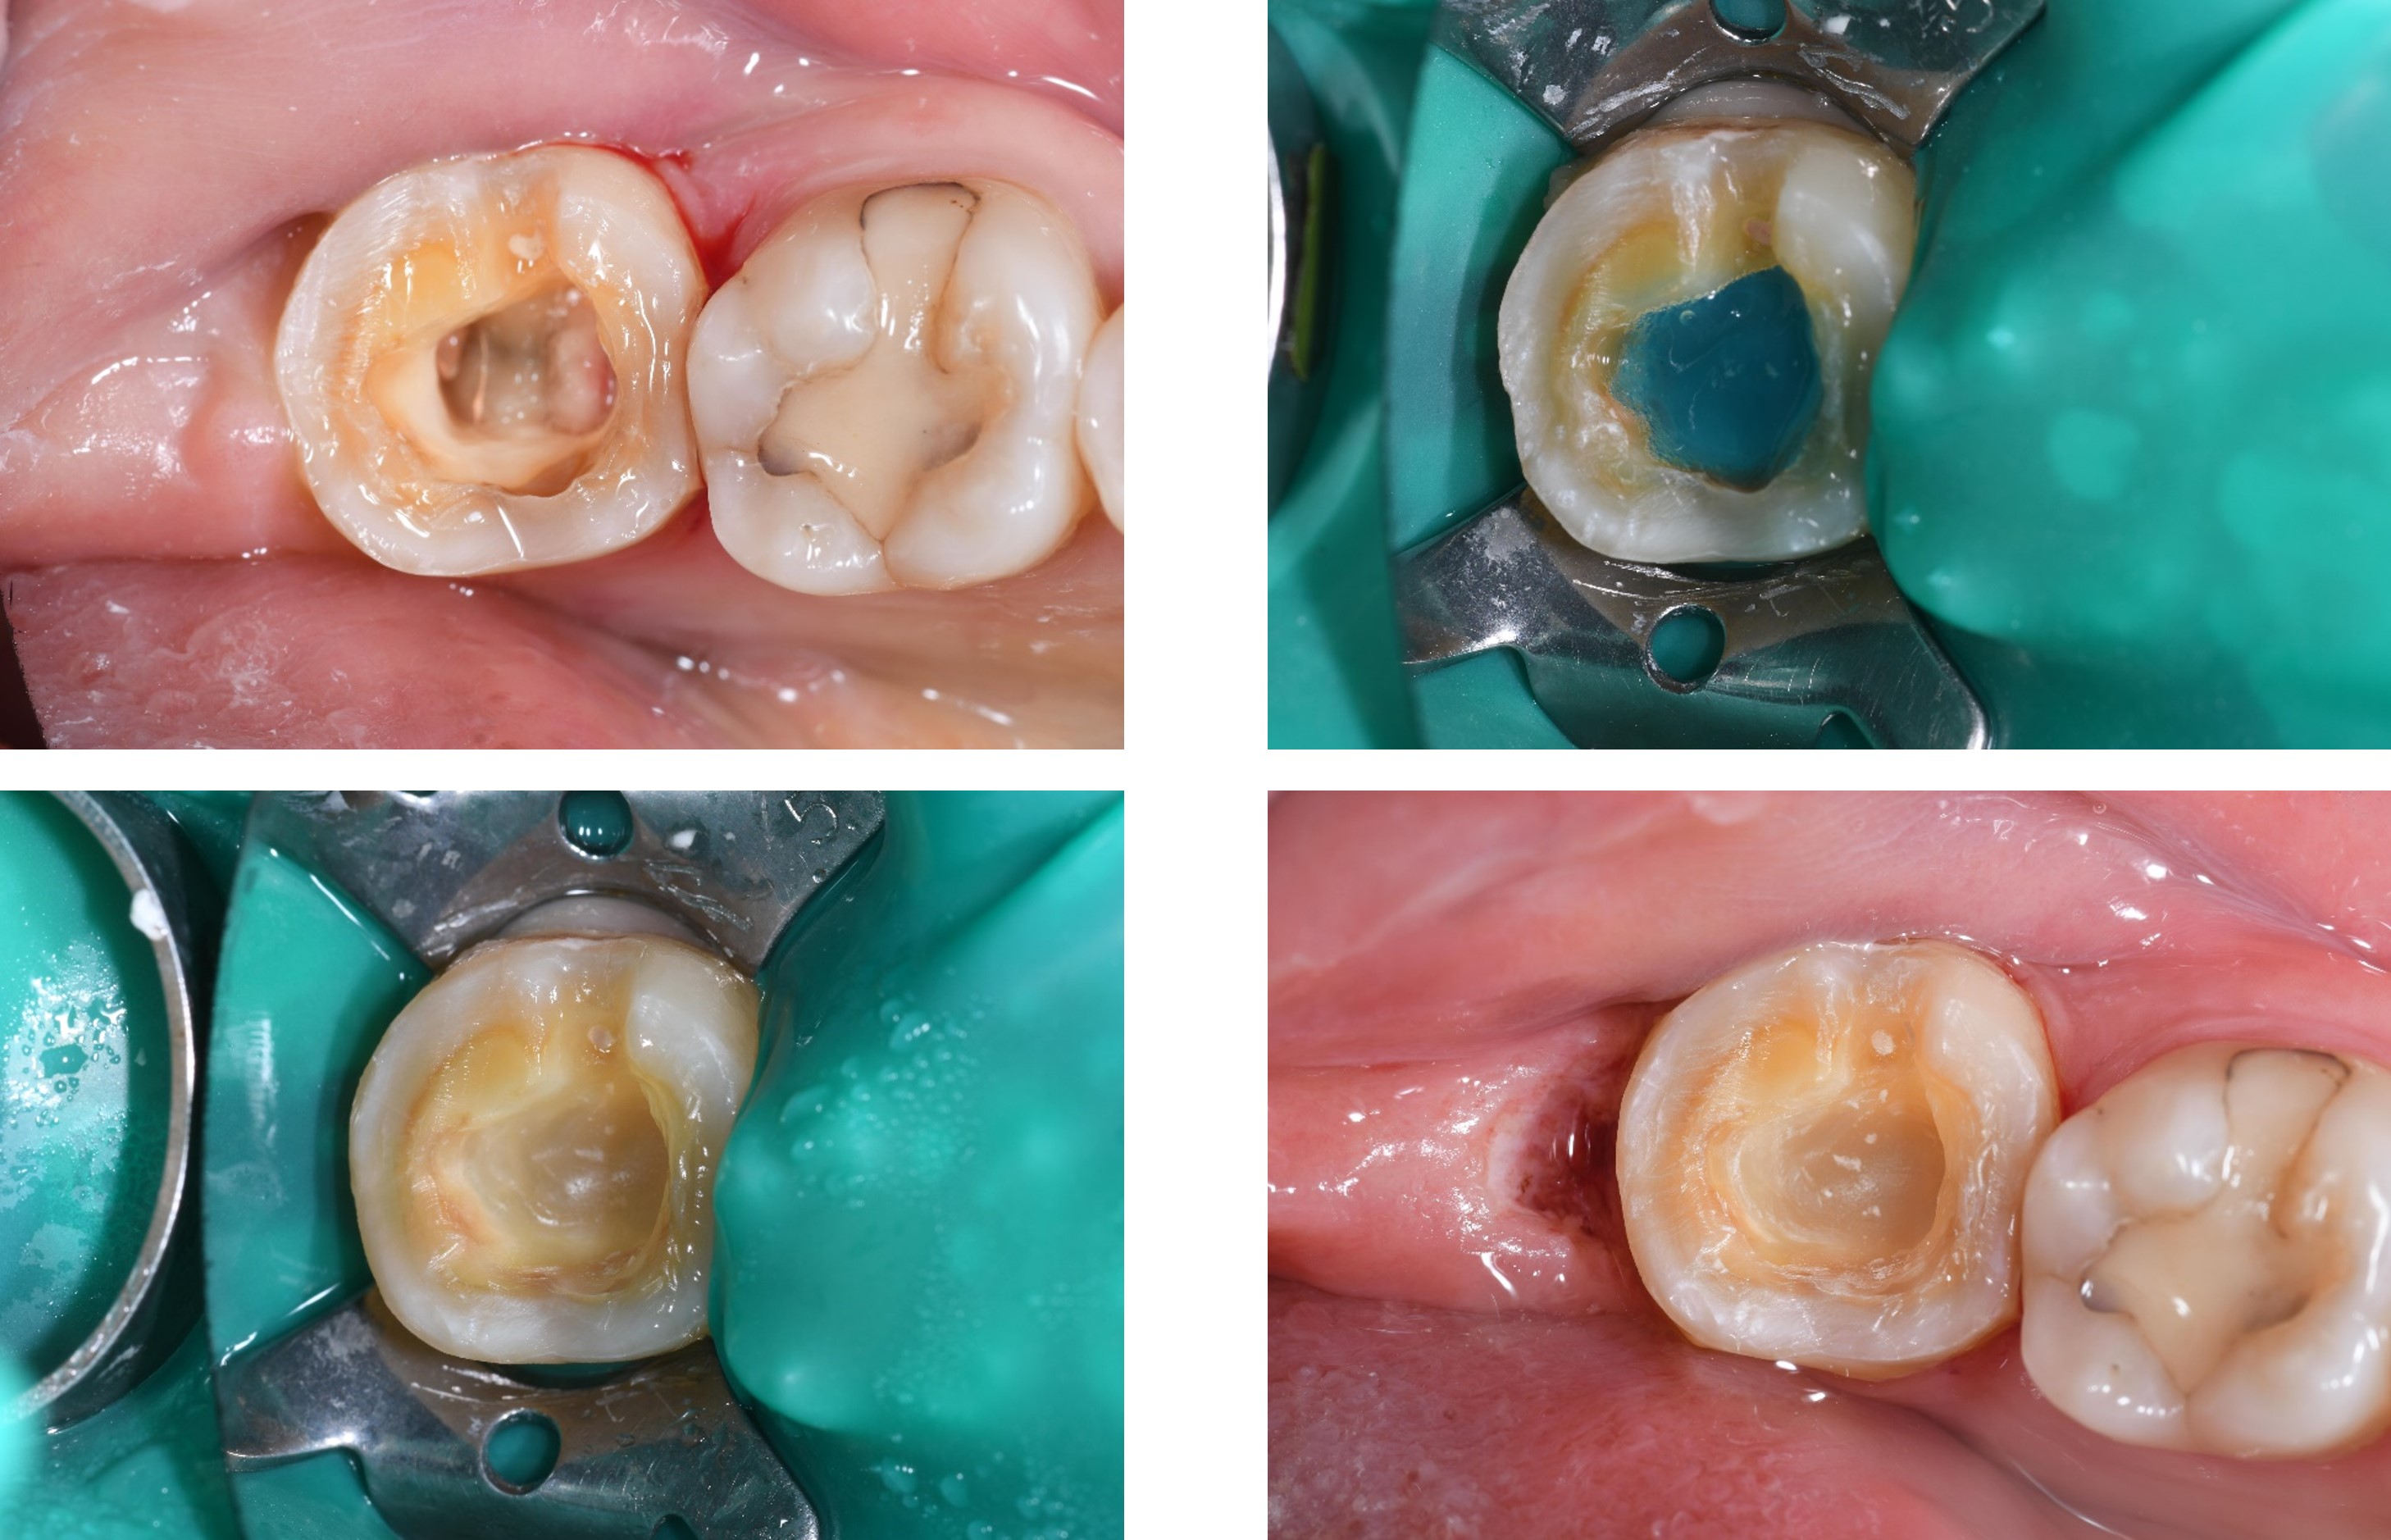

陶瓷黏著

治療後口內照

邊緣完整

術前、術後比較